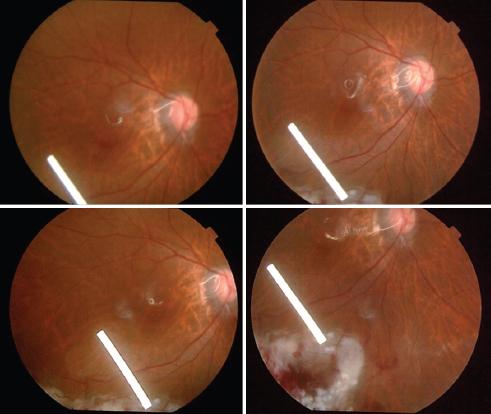

A partir de la primera semana de seguimiento se tomaron fotografías clínicas de fondo de ojo con una cámara TRC-NW7SF Mark II (Topcon Medical Systems, Inc., Paramus, NJ, USA). Se realizó una tomografía de coherencia óptica de dominio espectral (SD-OCT) (Heidelberg Engineering, Heidelberg, Alemania) de mácula para determinar la presencia o ausencia de membranas, pliegues y líquido subretiniano persistente e imágenes multicolor. El grosor foveal central fue determinado por algoritmos automatizados incorporados en el software de la SD-OCT Heidelberg (Figs. 1 a 4).

Figura 1 Fotografía de fondo de ojo del implante de dexametasona intravítreo en un paciente con desprendimiento de retina regmatógeno y vitreorretinopatía proliferativa de grado C, a la primera semana posoperatoria.

Figura 3 Fotografía de fondo de ojo de un paciente operado por desprendimiento de retina regmatógeno y vitreorretinopatía proliferativa de grado C en la periferia, a los 3 meses posoperatorios.